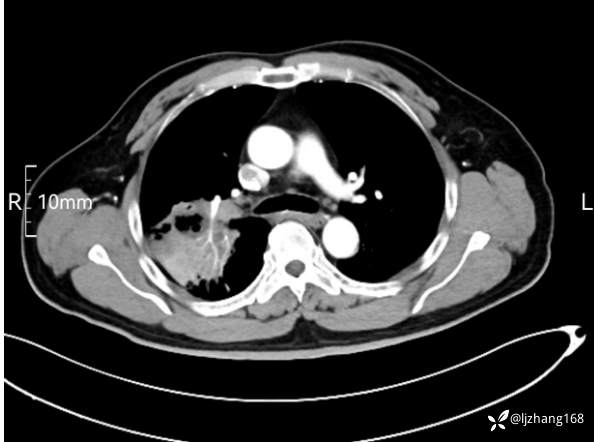

中年男患,右肺团片影,炎症0R肿瘤?

体格检查:T 36.4℃ P 110次/分 R 23次/分 BP 131/75mmHg。 自主体位,安静面容,神清合作,全身表浅淋巴结未触及,口唇无发绀,颈静脉无充盈,肝颈静脉回流征阴性。咽部未见充血、红肿,扁桃体不大,胸廓正常,双下肺叩诊清音,双肺呼吸音稍粗,右肺闻及少许湿性啰音,左肺未闻及湿性啰音,未闻及哮鸣音及胸膜摩擦音; 心界不大,心率110次/分,律齐,心尖部心音有力,各瓣膜听诊区未闻及杂音。腹软,无压痛、反跳痛及肌紧张,肝脾未及,移动性浊音阴性。双下肢不肿,神经系统未见明显阳性体征。

辅助检查:糖化血红蛋白12.3%。肺炎支原体IgG、IgM、呼吸道合胞病毒均未见明显异常。胸部CT:右肺上叶阻塞性肺炎。

讨论:诊断及鉴别